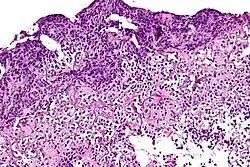

Lepromatous leprosy | Skin biopsy showing epidermal atrophy and multiple dermal infiltrates. | Category: Histopathology of leprosy | Leprosy |